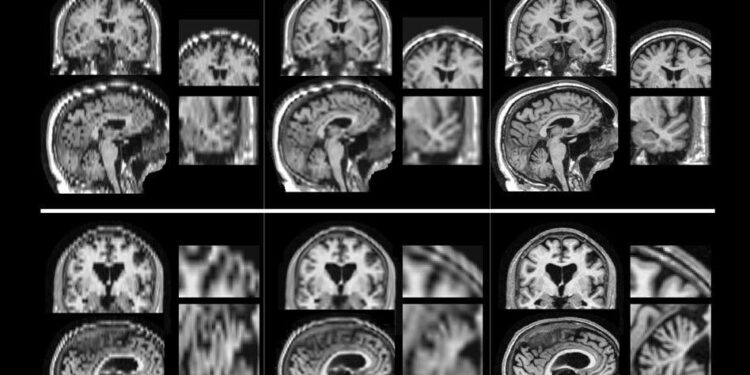

Recent advances in neuroimaging have peeled back the layers of mystery surrounding those moments when our minds unexpectedly go silent. Scientists have pinpointed that during a mental blank, there is a temporary disruption in communication between the prefrontal cortex and the hippocampus-two critical regions responsible for working memory and information retrieval. Functional MRI (fMRI) scans show reduced neural activity in these areas, suggesting that the brain’s executive functions are momentarily impaired. This breakdown impacts our ability to access stored information, creating the frustrating sensation of a ‘blank mind’ often experienced during high-pressure situations such as exams or public speaking.

Recent advancements in neuroimaging have transformed our understanding of those frustrating moments when the mind suddenly blanks. Cutting-edge techniques, such as high-resolution functional MRI and magnetoencephalography (MEG), allow scientists to observe brain activity in real-time with unprecedented detail. These tools reveal that cognitive interruptions are not random glitches but arise from dynamic shifts in neural network connectivity. Specifically, disruptions in communication between the prefrontal cortex-responsible for executive function-and the default mode network, which governs mind-wandering, appear to underpin these lapses.